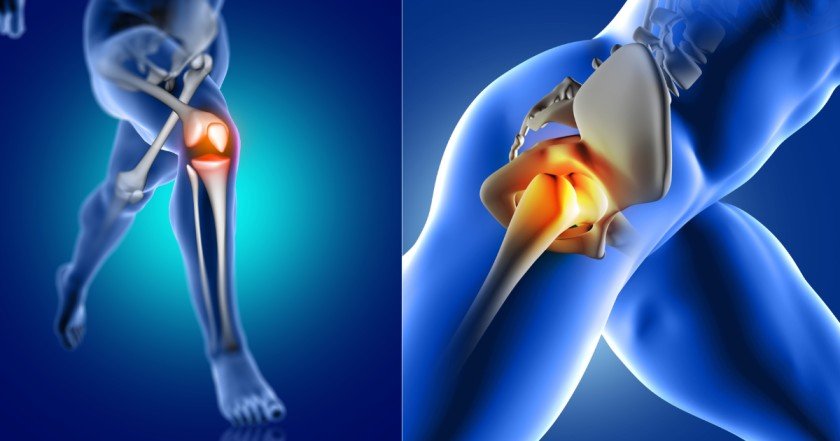

Joint Replacement in Nagpur has emerged as a transformative solution for patients struggling with chronic joint pain, stiffness, and restricted mobility. At Medivin Clinic, Dr. Vrushabh Kumbhare, a highly experienced orthopedic surgeon, offers precise and advanced joint replacement procedures designed to restore comfort, improve function, and enhance overall quality of life. Moreover, with his patient-centric approach and cutting-edge technology, he ensures safe, effective, and long-lasting results for every individual.

Understanding Joint Replacement

In modern orthopedics, joint replacement is considered one of the most reliable surgical treatments for severe joint degeneration caused by conditions such as osteoarthritis, rheumatoid arthritis, or traumatic injuries. This procedure involves replacing damaged or worn-out joint surfaces with artificial implants, thereby allowing smoother, pain-free motion. Furthermore, the technique has evolved significantly, ensuring faster recovery, minimal pain, and improved outcomes compared to traditional methods.

Types of Joint Replacement Surgeries

- Knee Replacement: Restores stability and motion in severely arthritic knees.

- Hip Replacement: Replaces damaged hip joints to improve mobility and reduce pain.